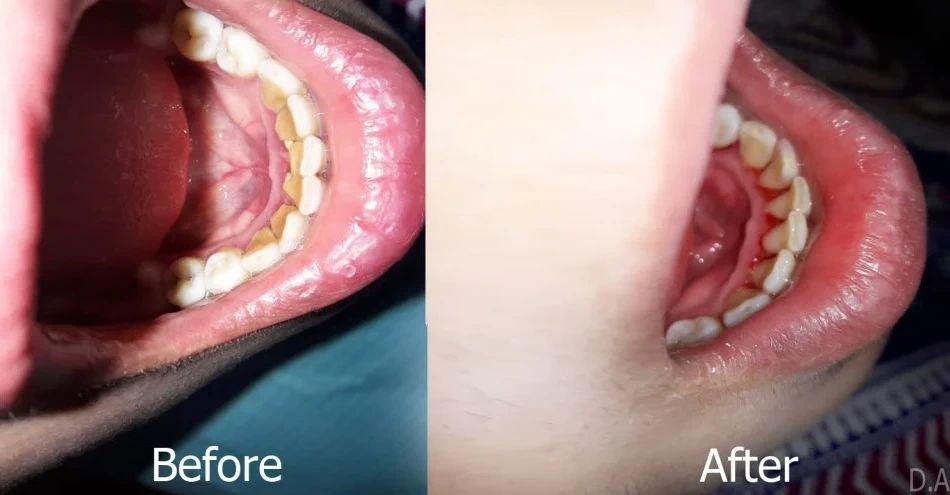

Treatment of periodontitis may include several steps, the first of which often requires the removal of the local causative factors which are in the form of plaque and hard calculus (both supragingival and subgingival) to create a biologically compatible environment between the teeth and the surrounding periodontal tissues, the gums and underlying bone. If left untreated, chronic inflammation of the gums and supporting tissues can raise a person’s risk of heart disease. Before beginning these procedures, the patient is generally numbed in the area intended for instrumentation. Because of the deeper nature of period scaling and root planning, either one-half or one-quarter of the mouth is generally cleaned during one appointment. It is typically not recommended to have the entire mouth scaled at one appointment because of the potential inconveniences and complications of numbing the entire mouth.

After Scaling

Following scaling, additional steps may be taken to ensure disinfection of the periodontic tissues. Oral irrigation of the tissues may be done using chlorhexidine gluconate solution, which has high substantivity in the oral tissues. This means that unlike other mouthwashes, whose benefits end upon expectorating, the active antibacterial ingredients in chlorhexidine gluconate infiltrate the tissue and remain active for a while. However effective, chlorhexidine gluconate is not meant for long-term use. Site-specific antibiotics may also be placed in the periodontic pocket following scaling and root planning to provide additional healing of infected tissues. This allows the medication to seep into the tissues and destroy bacteria that may be living within the gingiva, providing even further disinfection and facilitation of healing.

Scaling and root planning procedures are to be considered effective if the patient is subsequently able to maintain his/her periodontal health without further bone or attachment loss. The long-term effectiveness of scaling and root planning depends upon several factors. These factors include general patient health, patient compliance, disease progress at the time of intervention, probing depth, and anatomical factors like grooves in the roots of teeth, concavities, and furcation involvement which may limit the visibility of underlying deep calculus and debris. The more severe the infection is before the intervention, the greater the effort is put in by our periodontists to arrest its progress and return the patient to health.